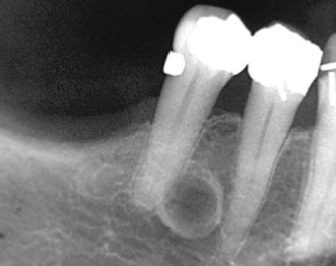

Describe the radiographic features of this Buccal Bifurcation Cyst?

Buccal Bifurcation of Molars

Roots Displaced Lingually

Occlusal Plane Inclined Buccally

Lingual Cusp Higher on BWs and PAs